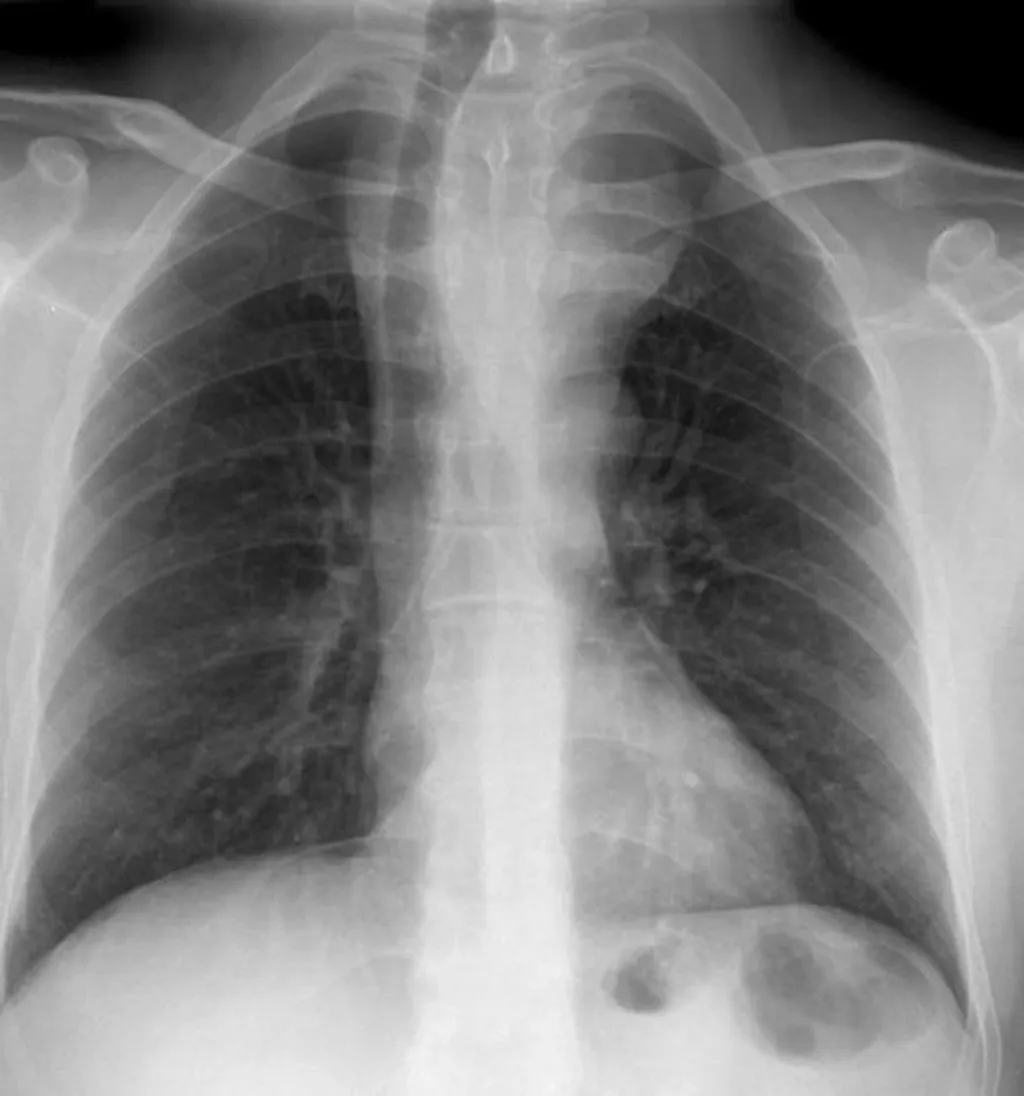

കഴുത്തിന്റെയും നെഞ്ചിന്റെയും

എക്സ്-റേ പരിശോധന

ശ്വാസനാളത്തിന്റെ വ്യാസം, ദിശമാറ്റം, അന്നനാളത്തിൽ ഉണ്ടാകുന്ന വ്യതിയാനം, തൈറോയ്ഡ് ഗ്രന്ഥി വളർന്ന് കഴുത്തിലേക്ക് അധികരിച്ചിട്ടുണ്ടോ എന്നറിയാൻ കഴുത്തിന്റെ എക്സ്-റേ കൊണ്ട് സാധിക്കുന്നു. കൂടാതെ കഴുത്തിലെ കശേരുക്കളുടെ രോഗാവസ്ഥ മനസ്സിലാക്കാനും ഇത് ഉപകരിക്കുന്നു. നെഞ്ചിന്റെ എക്സ്-റേ നെഞ്ചിലേക്ക് തൈറോയ്ഡ് വളർന്നുവരുന്ന അവസ്ഥ (Retro Sternal goitre) മനസ്സിലാക്കുന്നതിനും ശ്വാസകോശങ്ങളുടെയും ഹൃദയത്തിന്റെയും രോഗാവസ്ഥ മനസ്സിലാക്കാനും ഉപകരിക്കുന്നു.